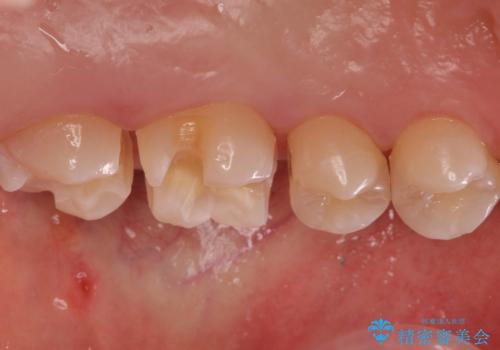

歯と歯の間の虫歯 インレーでの治療(セラミック・ゴールド)

- 銀歯のやり替えと虫歯の治療をご希望で来院された患者様です。

一番奥の歯は外から見えにくい部分であるためゴールドインレーで修復します。

その他はセラミックインレーで修復します。

- 左上46:セラミックインレー/77,000円×2 左上7:ゴールドインレー/77,000円×1費用は治療当時の料金となります